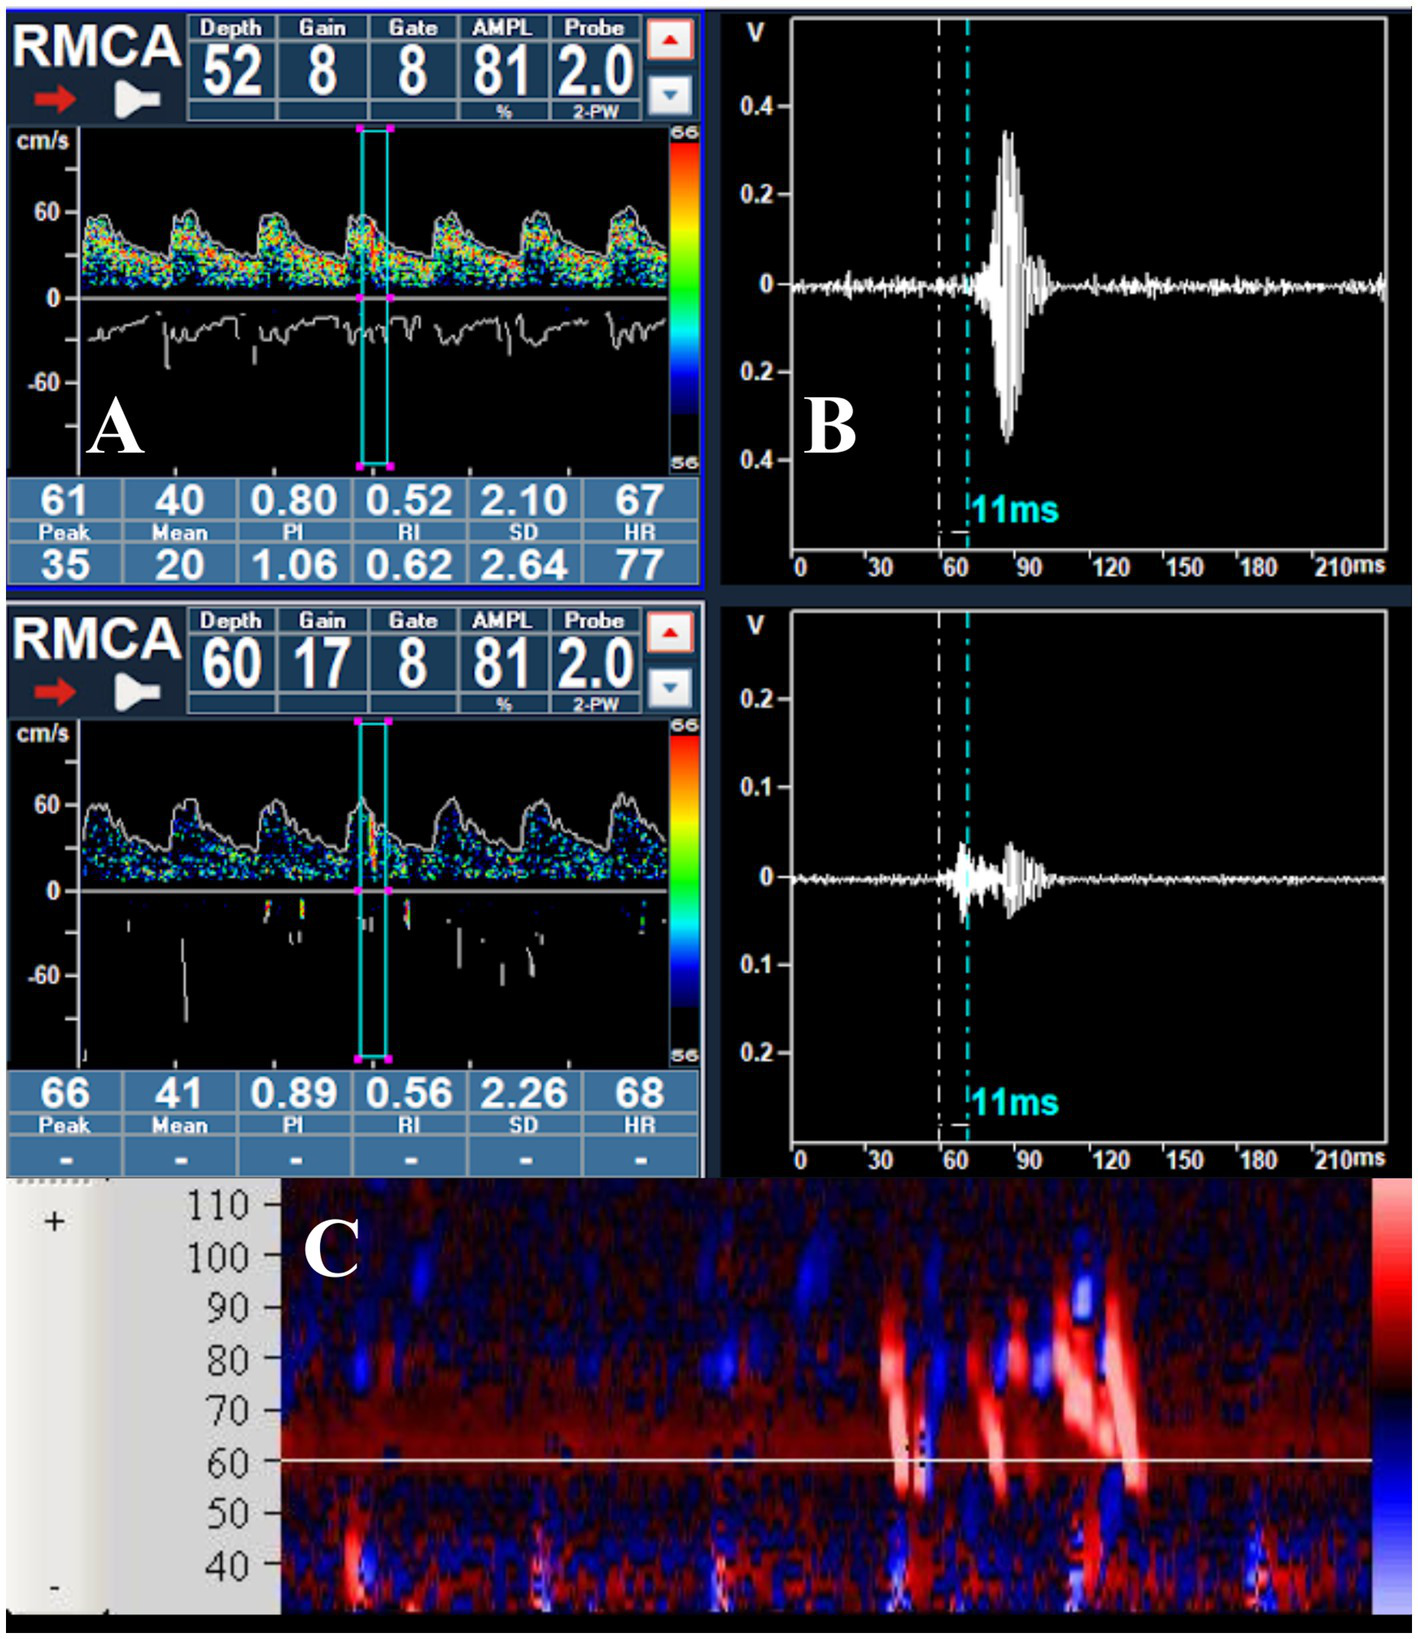

All signals detected by transcranial Doppler as either microembolic events or artifacts are stored by the system and can be reviewed offline. The signal log specifies whether the event was classified as an embolus or artifact, its signal intensity, and—when bilateral monitoring is performed—the artery of origin. The operator can review each detected signal in three different modes: within the Doppler spectrum (Figure 2A), in M-mode (Figure 2C), or as raw data (Figure 2B); in addition, the acoustic output of each signal can typically be replayed for auditory verification.

Figure 2

(A) Passage of a microbubble visualized within the Doppler spectrum during the right middle cerebral artery monitoring; (B) raw data of the MB, showing the delay in appearance at a depth of 52 mm; (C) visualization of a series of MBs in the M-mode.